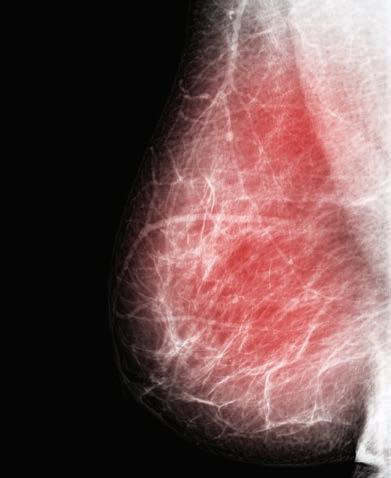

Keeping abreast of cancer care

With GPs recently updated on the prevention and early detection of breast cancer, debate about how to manage breast density has come under the spotlight once again.

The statistics for breast cancer in Australia are sobering. Not only is it the most common cancer in women – responsible for more than 21,000 new cases a year – it is also the second leading cause of death.

The lifetime risk of the disease is now nudging one in seven for women by the age of 85 – compared to about one in 12 in the 1990s – and there has been an increase in cases in younger women.

Breast density role

The latest RACGP breast cancer advice weighs into the ongoing debate about managing breast density – the proportion of fibroglandular tissue measured on a mammogram.

Dense breast tissue, like cancer, appears as white on a mammogram, making it hard to pick up cancer and potentially delaying diagnosis and resulting in more advanced cancers. It is also itself an independent risk factor for developing the disease.

Breast density is not related to breast size or the ‘breast aware’ message promoted to women because it cannot be determined by feel or touch.

About 10% of Australian women have extremely dense breasts and they are four to six times more likely to get breast cancer than those with fatty breasts.